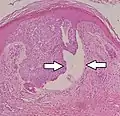

Micrograph of a basal-cell carcinoma, showing the characteristic histomorphologic features (peripheral palisading, myxoid stroma, artefactual clefting). H&E stain

Basal-cell carcinomas are currently considered to have origin from the folliculo-sebaceous-apocrine germ, also known as trichoblast. The differential diagnosis with trichoblastic carcinoma, a rare malignant form of trichoblastoma, can be challenging.[9] Alternatively, one argument is that basal-cell carcinoma is trichoblastic carcinoma.[10] Overexposure to sun leads to the formation of thymine dimers, a form of DNA damage. While DNA repair removes most UV-induced damage, not all crosslinks are excised. There is, therefore, cumulative DNA damage leading to mutations. Apart from the mutagenesis, overexposure to sunlight depresses the local immune system, possibly decreasing immune surveillance for new tumor cells.